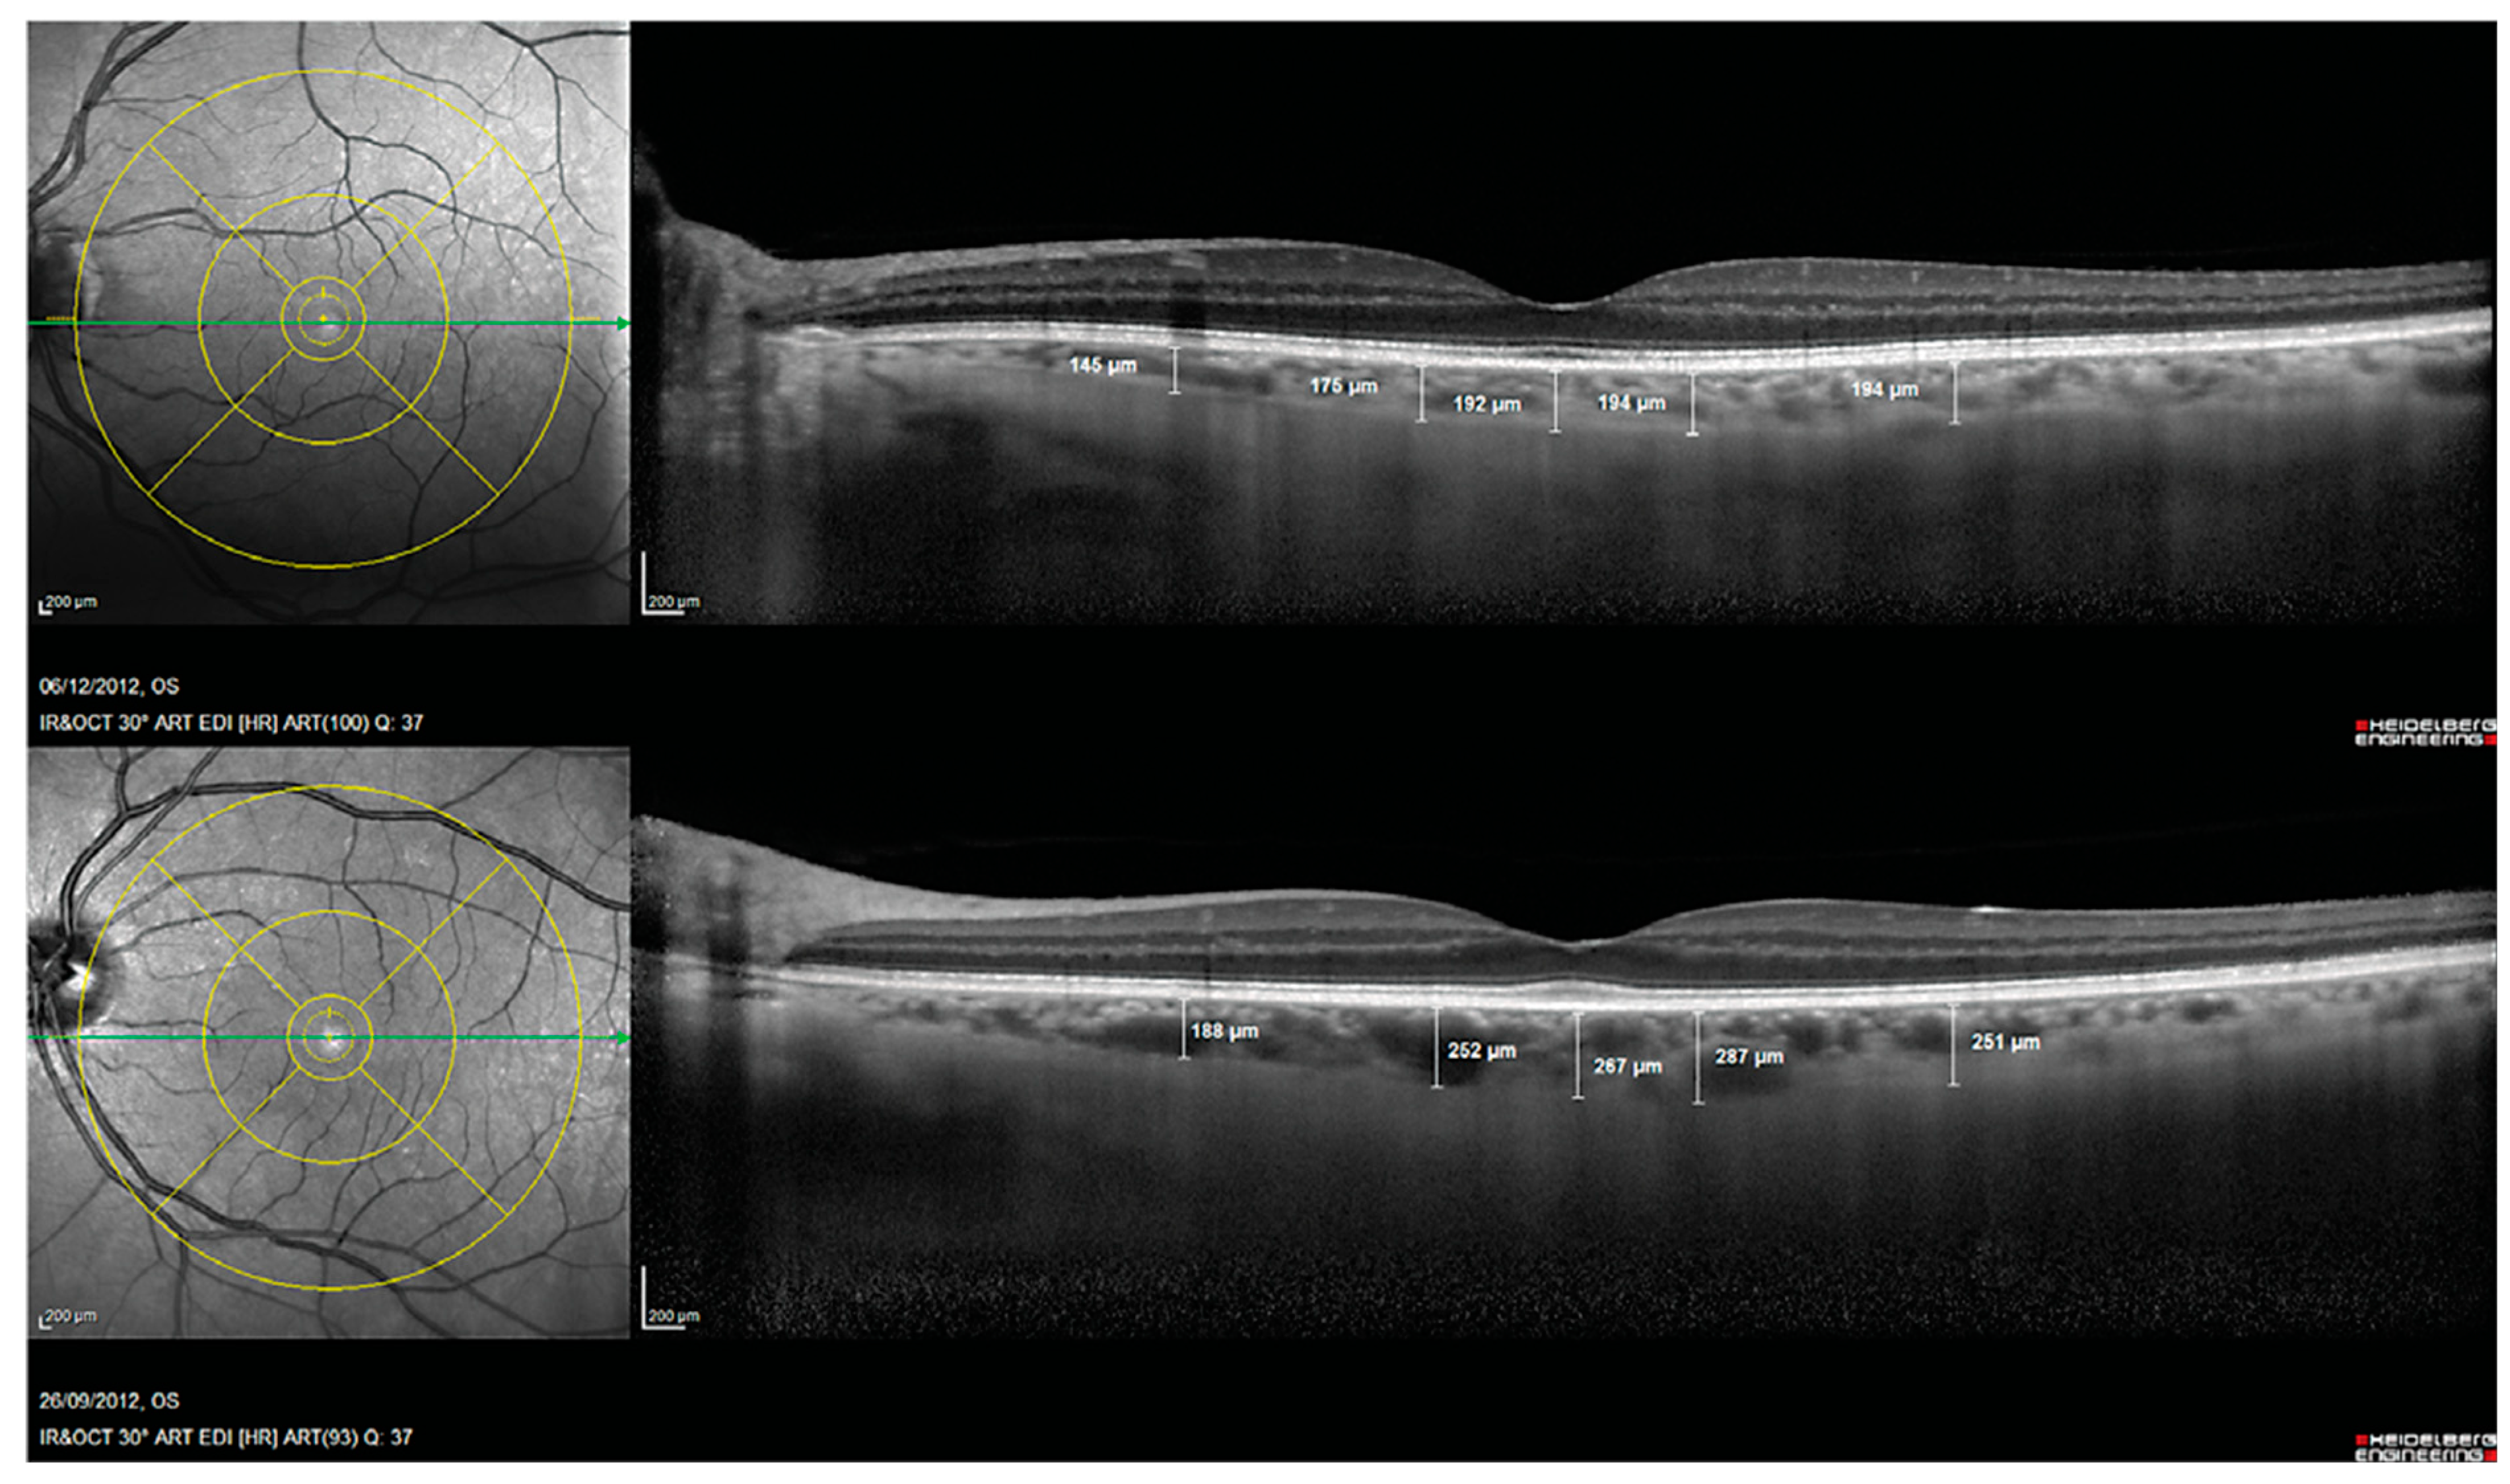

- Bayhan, H.A.; Aslan Bayhan, S.; Celikbilek, A.; Tanık, N.; Gürdal, C. Evaluation of the chorioretinal thickness changes in A lzheimer’s disease using spectral-domain optical coherence tomography. Clin. Exp. Ophthalmol. 2015, 43, 145–151. [Google Scholar] [CrossRef]

- Gharbiya, M.; Trebbastoni, A.; Parisi, F.; Manganiello, S.; Cruciani, F.; D’Antonio, F.; De Vico, U.; Imbriano, L.; Campanelli, A.; De Lena, C. Choroidal thinning as a new finding in Alzheimer’s disease: Evidence from enhanced depth imaging spectral domain optical coherence tomography. J. Alzheimer’s Dis. 2014, 40, 907–917. [Google Scholar] [CrossRef]

- Trebbastoni, A.; Marcelli, M.; Mallone, F.; D’Antonio, F.; Imbriano, L.; Campanelli, A.; de Lena, C.; Gharbiya, M. Attenuation of choroidal thickness in patients with Alzheimer disease. Alzheimer Dis. Assoc. Disord. 2017, 31, 128–134. [Google Scholar] [CrossRef]